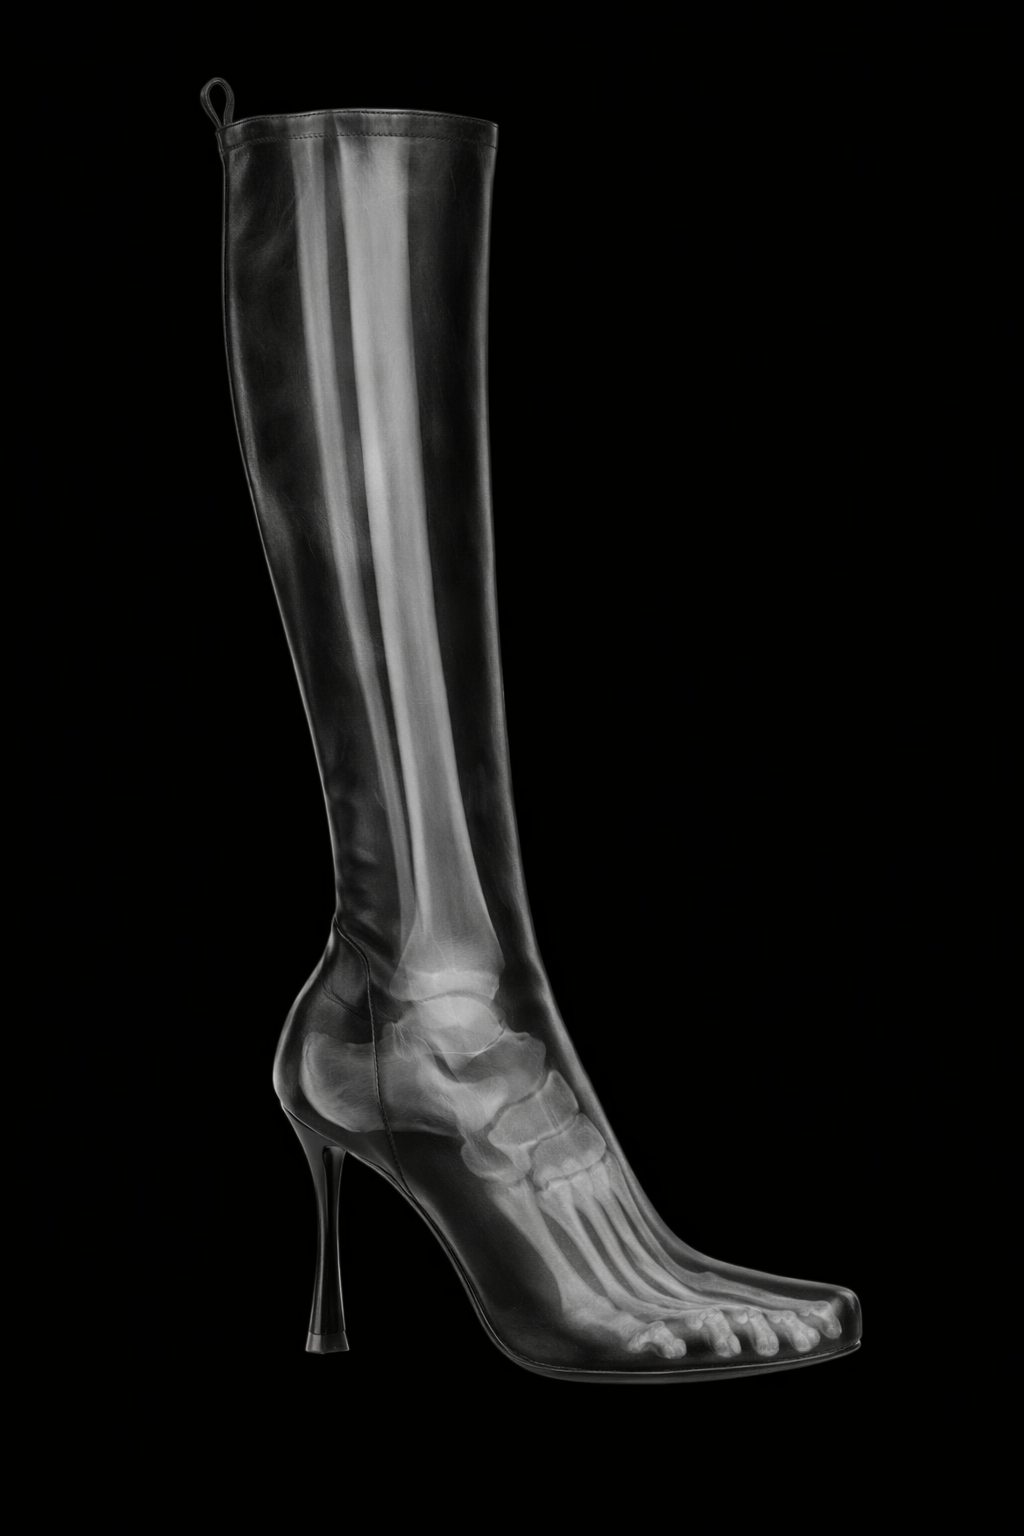

STORY — WHYA monochrome boot designed as a wearable scan.You’re seeing someone deeply — without knowing them.X-rays reveal the human body from a perspective the naked eye will never access. They remove identity, surface, and performance, leaving only structure. This project takes that hidden truth and refuses to keep it invisible. What is normally diagnostic becomes declarative. The body is no longer beneath the product — it is fused into it.

DESCRIPTION — WHAT YOU’RE SEEINGThe first image is an X-ray scan of the human boot — a medical view translated into material. That scan is printed directly onto the boot’s surface, aligning anatomy to form with surgical precision.The skeletal structure of the foot is fully exposed: phalanges, metatarsals, calcaneus, arch. The image continues upward, revealing the tibia and fibula, extending the scan beyond the foot into the lower leg — a complete anatomical read, embedded into a monochrome shell.The boot becomes an interface between body and object. Cold, high-contrast imaging collides with industrial footwear. Clinical data becomes aesthetic. Protection becomes transparency.The result feels illicit and futuristic — medical imaging weaponized into fashion. A post-human artifact where the body is not hidden, but permanently mapped.